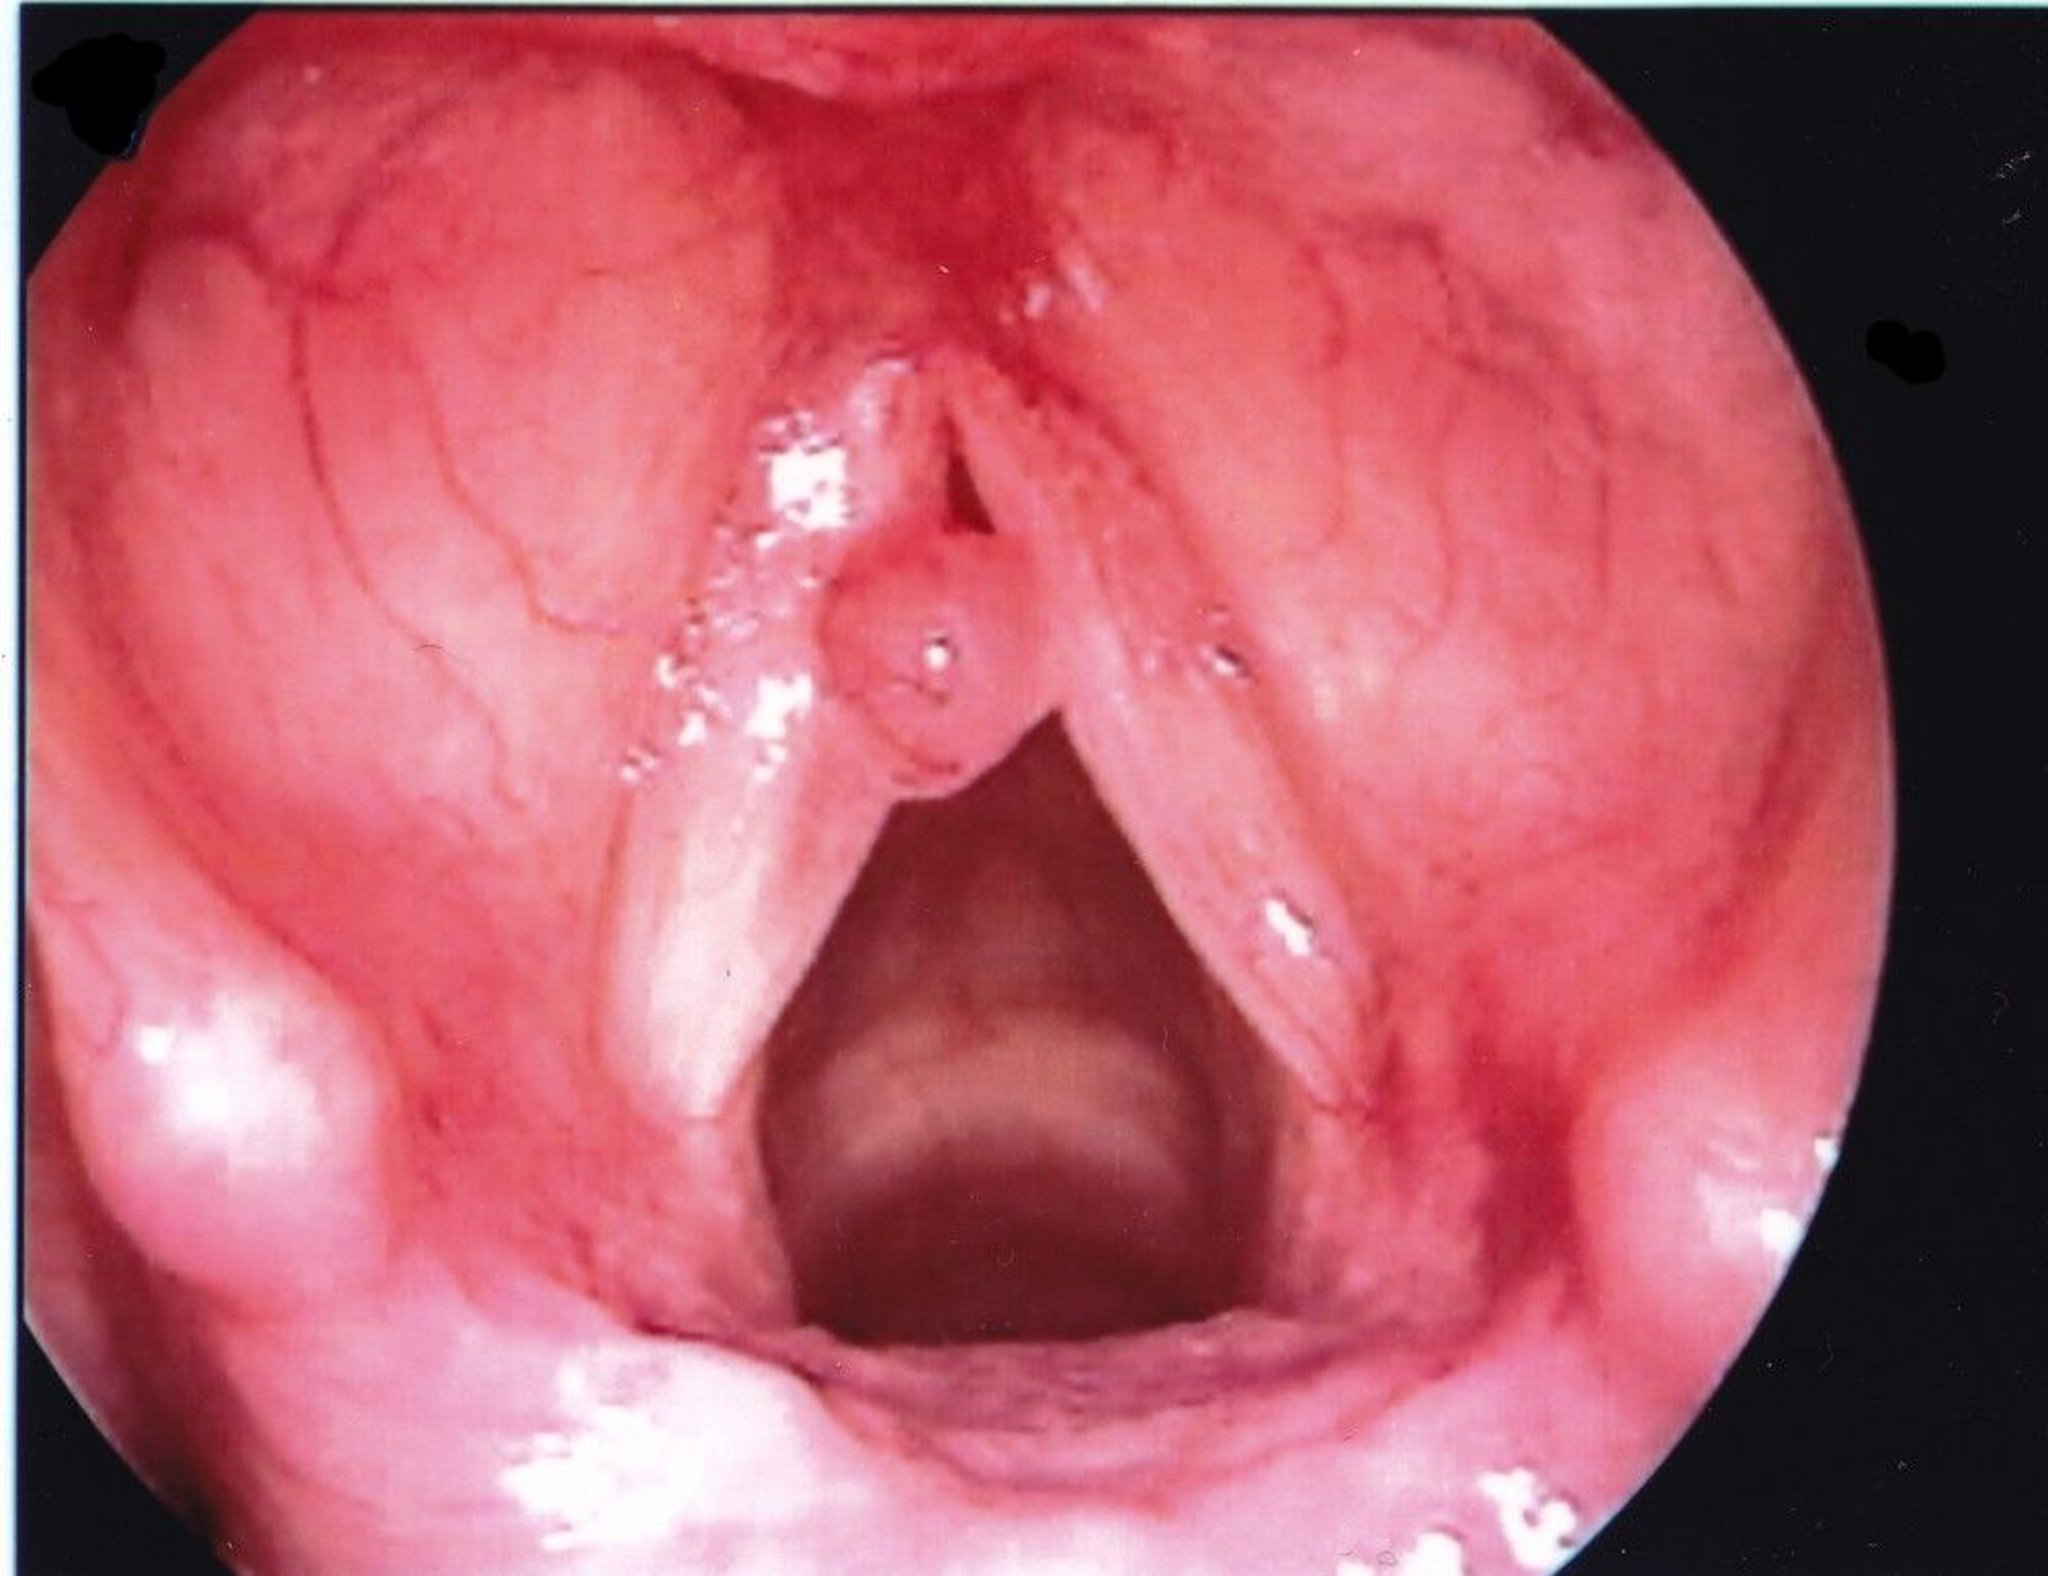

Vocal Fold Polyp

A vocal fold polyp usually appears unilaterally and larger than a nodule.

Image provided by Eiji Yanagisawa, MD.